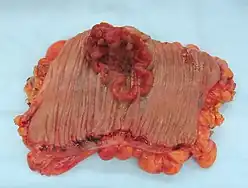

An invasive colorectal carcinoma (top center) in a colectomy specimen

An invasive colorectal carcinoma (top center) in a colectomy specimen -